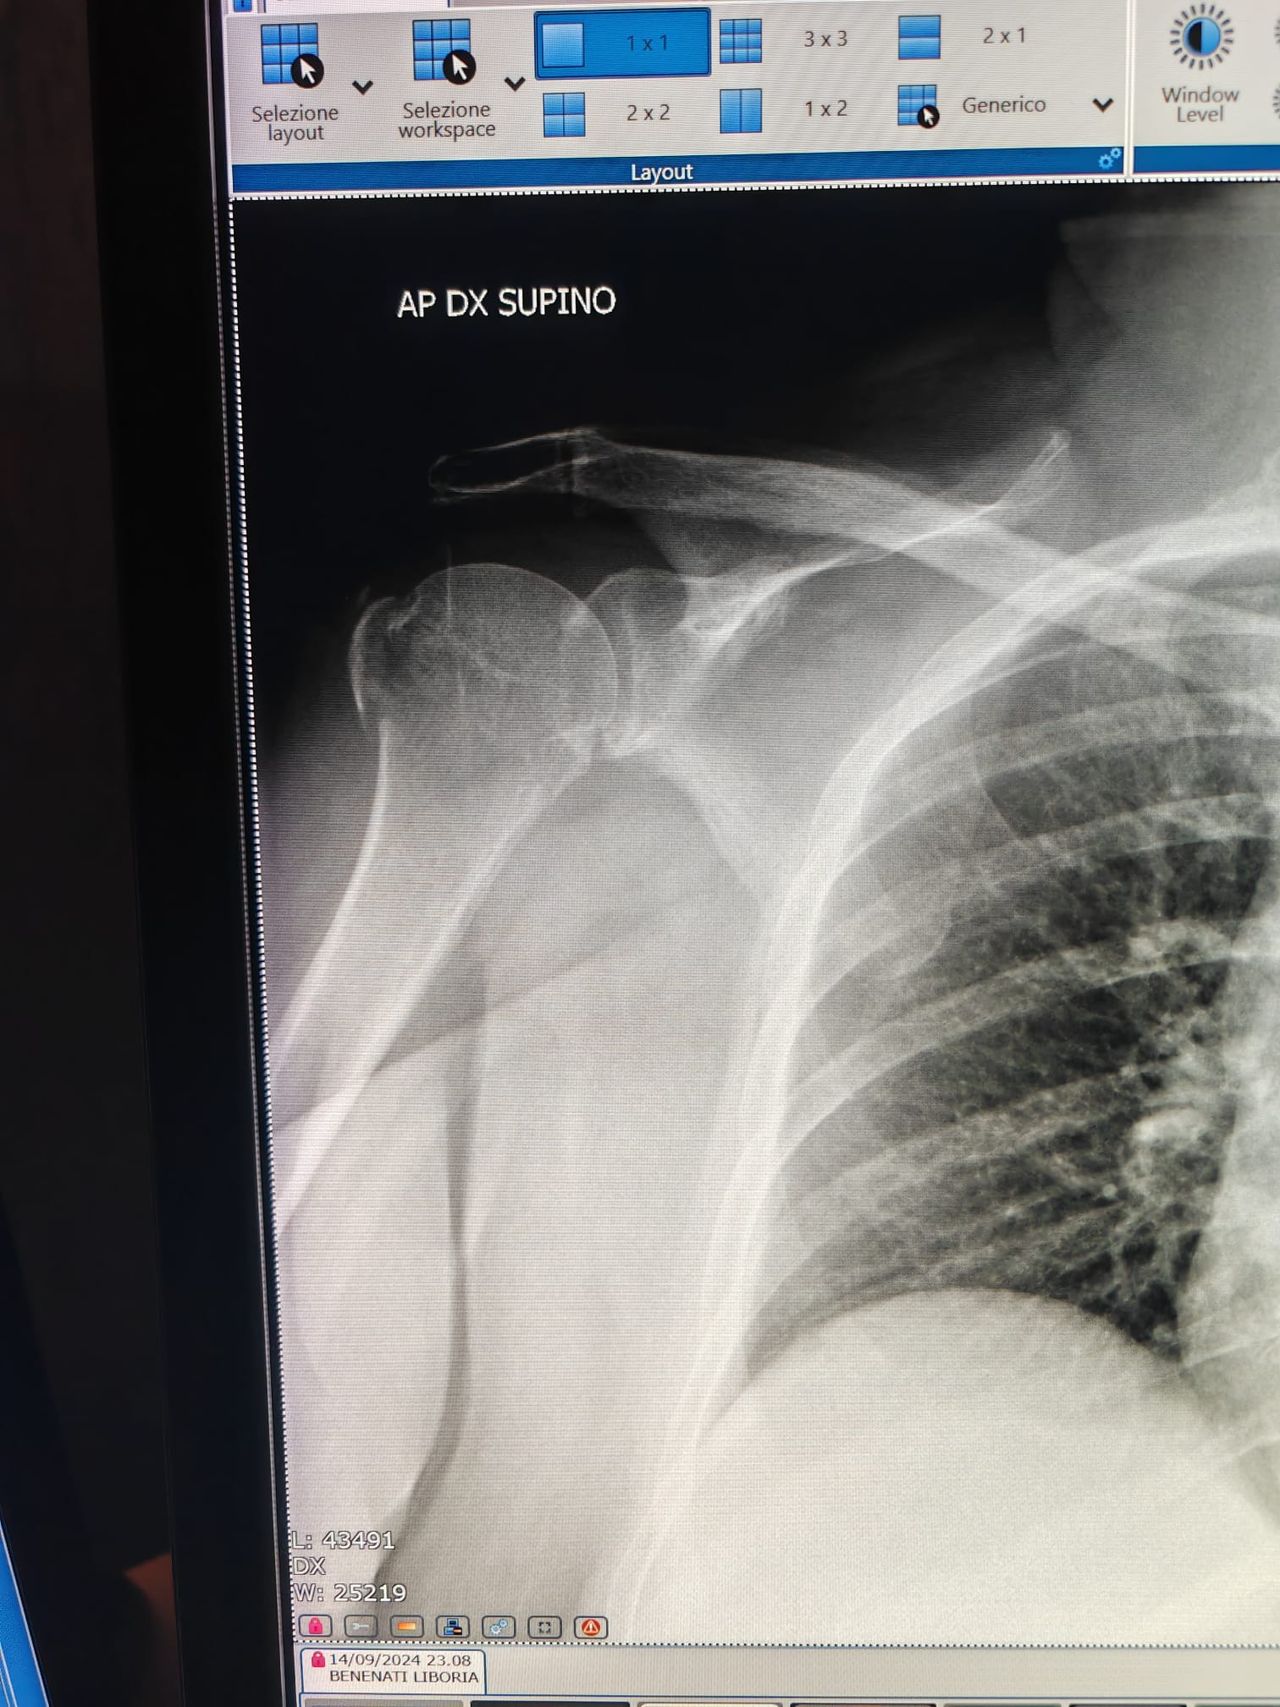

Ho partecipato a cadaver- lab presso il polo Universitario di Berlino sul trattamento delle fratture vertebrali secondo tecnica di vertebroplastica e cifoplastica, sul trattamento chirurgico delle fratture di spalla e di gomito.

Mi occupo del trattamento delle patologie della spalla, compreso il trattamento delle fratture e della lesione della cuffia dei rotatori e del successivo recupero funzionale conservativo.

Consulto online chiaro ed esaustivo richiesto per una frattura all'omero.

Il Dott. Giannuzzo è stato attento e professionale nell'affrontare la tematica, dedicando il tempo necessario sia ad esporre l'eventuale gestione del caso, che a rispondere alle domande a lui poste.

Non esiterei a riaffidarmi alle sue competenze, grazie ancora.